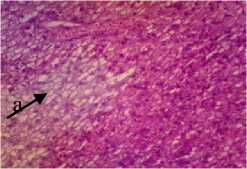

Berdasarkan dari hasil pengamatan histopatologi kulit ikan kerapu cantang yang diberi deterjen 0,25gr/l menunjukkan adanya perubahan yaitu mengalami degenerasi vakuola. Degenerasi vakuoa pada kulit ditandai dengan vakuola yang membesar pada sitoplasma (Chusniati dkk., 2006). Jika dilihat pada Gambar 1, nampak ruang-ruang kosong pada sitoplasma.

Pada pemberian ekstrak P. australis dengan dosis 0,5% dan 1% struktur jaringan kulit tidak mengalami perubahan yaitu masih mengalami degenerasi vakuola sedangkan pada pemberian

Gambar 3. Struktur Jaringan Kulit Ikan Kerapu Cantang (Epinephelus fuscoguttatus lanceolatus). Keterangan: D: Degenerasi Vakuola (a) (400x), P1: Degenerasi Vakuola (a) dan Hiperplasia (b) (400x), P2: Degenerasi Vakuola (a) (400x), P3: Degenerasi Vakuola (a) dan Sel Radang (c) (400x).

dengan dosis 1,5% mengalami perubahan yaitu ukuran vakuola pada jaringan berkurang dan terjadi infiltrasi atau peradangan. Herdiani dan Putri (2018) menyatakan bahwa peradangan berfungsi untuk menghancurkan atau membatasi agen yang merugikan lalu memulihkan dan mengganti jaringan yang rusak.